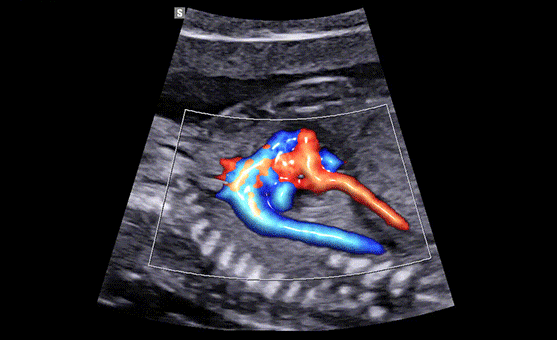

Expresión detallada de la dinámica del flujo sanguíneo

El rendimiento del color CrystalLive ha sido mejorado para visualizar claramente la hemodinámica del flujo sanguíneo. La mayor sensibilidad resultante del nuevo procesamiento de la señal de color permite una detección precisa de los vasos sanguíneos periféricos, los flujos sanguíneos micro circulatorios y los volúmenes de flujos sanguíneos lentos.

Mostrar el flujo sanguíneo en los vasos en apariencia 3D

Doppler en color con LumiFlow (vista de 4 cámaras)

LumiFlow es una función que visualiza el flujo sanguíneo en apariencia dimensional para ayudar a comprender la estructura del flujo sanguíneo y los vasos pequeños de forma intuitiva.